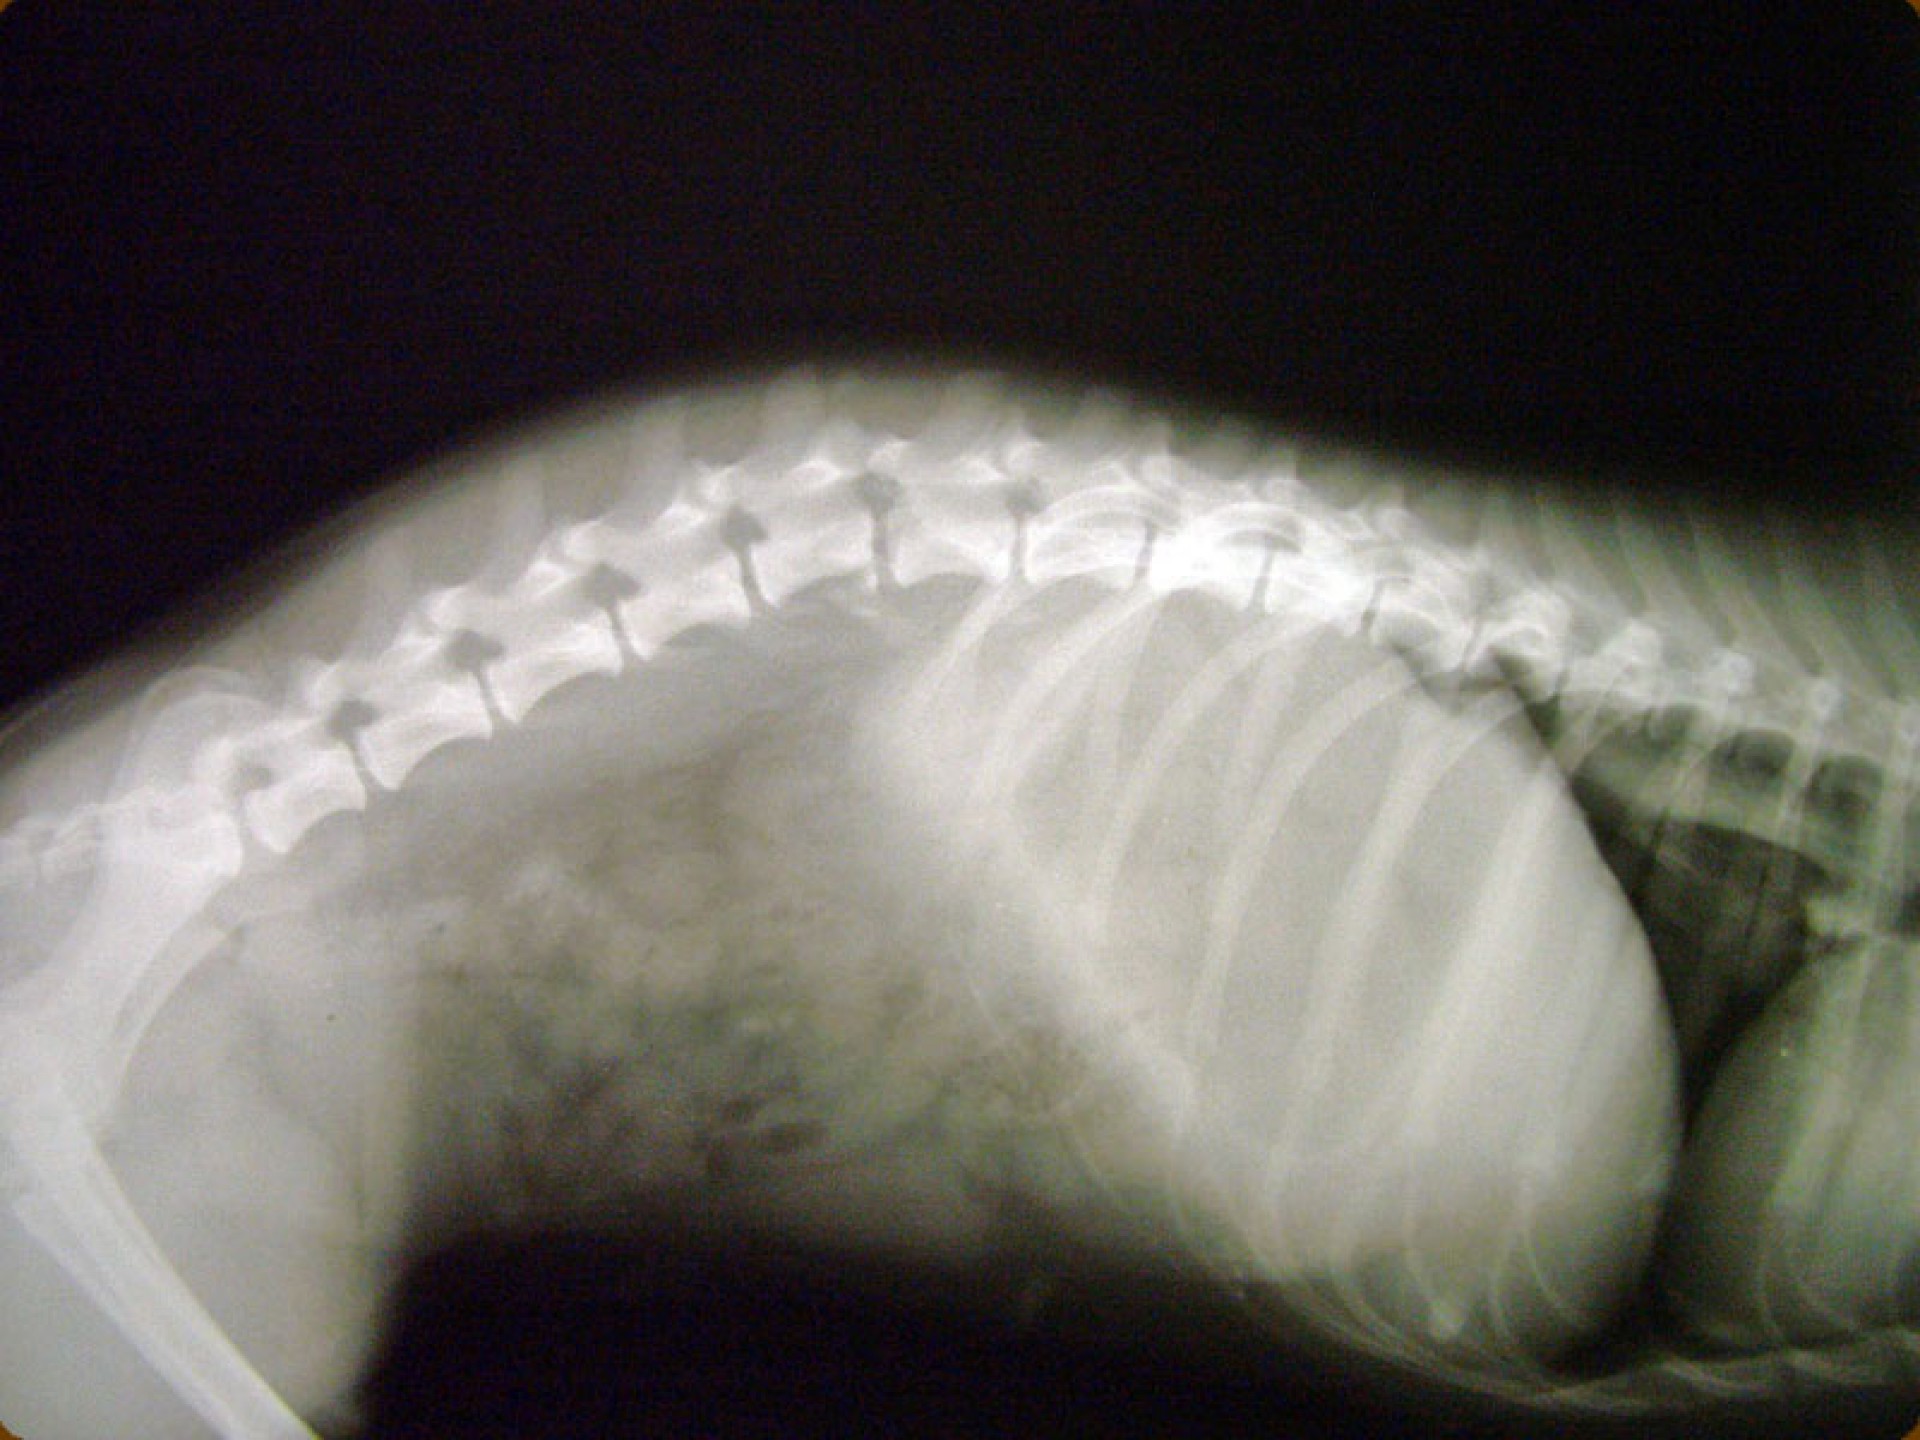

A gerinctörés diagnózisának felállítása komoly döntés elé állítja a tulajdonost és az állatorvost egyaránt. A gerinctörés következtében a gerincvelő minden esetben enyhébb-súlyosabb mértékben sérül. A gerincvelő sérülésének mértékét neurológiai vizsgálattal állapítjuk meg, de a diagnózis felállításához nélkülözhetetlen röntgen felvételről is már információt nyerhetünk a gerincvelő várható állapotáról. A tört végek egymáshoz képest történő kis mértékű elmozdulása esetén a gerincvelő körüli területek bevérzése miatt kialakult neurológiai tünetekkel találkozunk míg nagymértékű elmozdulásuk a gerincvelőt gyakorlatilag olló szerűen elnyírhatja. Így a natív röntgen felvételen a gerinccsatorna elmozdulásából már következtetést vonhatunk le a gerincvelőt ért sérülés mértékéről. A gerincvelő tényleges állapotáról azonban csak neurológiai vizsgálattal győződhetünk meg!

A gerinctörések műtéti ellátása kettős feladatot jelent: egyrészről a törés és elmozdulás következtében kialakult gerincvelő összenyomatást kell megszüntetni, másrészről a tört végeket kell adaptálni és eredeti állapotban - a további elmozdulás megakadályozása érdekében - rögzíteni. A műtéti ellátás során ezért minden esetben az érintett területen a gerinccsatorna felső csontos ívét eltávolítjuk (total laminectomia) így a gerincvelő sérülésének mértéke egyértelműen látható ill. a későbbi összenyomatása elkerülhető.

A törött csigolyatestek adaptációja és rögzítése a nyitott gerinccsatorna mellett komoly kihívást jelent. A későbbi elmozdulás elkerülésére többféle műtéttechnika alkalmazható, melyek közül a csigolyatestek lemezes osteosynthesise ill a fixateur interna használata terjedt el leginkább. Első esetben a sérülés előtti és mögötti csigolyákat lemez és csavarok segítségével egymáshoz rögzítjük, míg az utóbbi esetben a törés előtti és mögötti egy vagy több csigolyatestet két oldalról behelyezett csavarok és egy steril kétkomponensű akrilát műgyanta segítségével rögzítjük.